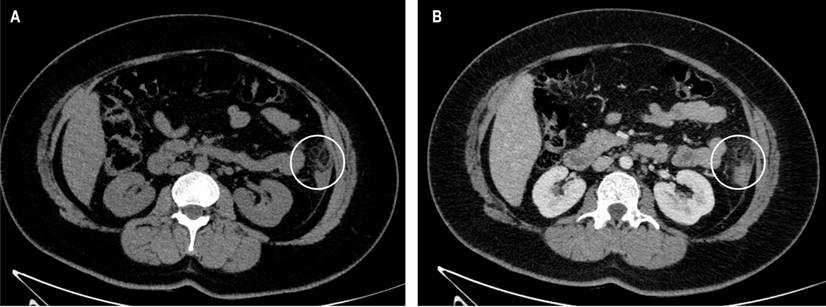

The patient underwent an abdominopelvic computed tomography (CT) with contrast material, which evidenced that the liver, pancreas, spleen, and intestinal loops did not have any significant alteration, the stomach was partially distended with preserved walls and with a hypodense image of the oval fat density of 25 mm x 16 mm that contacts the anterior border of the descending colon, which contains inside a hyperdense image (the sign of the central point) compatible with EA (Figures 1, 2 and 3). She started her medical treatment for pain with diclofenac 75 mg intramuscularly every twelve hours, paracetamol 500 mg orally in only one dose, metronidazole 500 mg orally every eight hours, and simethicone (gaseovet) 15 drops every eight hours. She was indicated to have a soft low-fat diet. The patient was discharged after two days on the following medications: paracetamol 500 mg (10 tablets), tramadol 50 mg (4 tablets), metronidazole 500 mg (9 tablets), and metoclopramide 10 mg (9 tablets).

EA commonly begins with pain in the lower left quadrant (40%-60%), pain in the right lower quadrant (40%-50%), and pain in other locations, including the upper right and left quadrants (1.5%-10%).11 An increase in white blood cells can hardly be found, so the possibility of laboratory aid, including their symptomatological nonspecificity, is dismissed, leading physicians to an incorrect diagnosis. Therefore, the chosen study is CT, and only 2.5% are diagnosed with the symptoms before surgery since normal epiploic appendages are not evident on CT but can be detected when inflamed or delineated by ascites.12 Key features in CT include an ovoid lesion of fat density, also known as the hyperattenuating ring sign, mild thickening of the intestinal wall, and a central focus of high attenuation within the fat lesion that in recent studies has been described as the central point sign.12